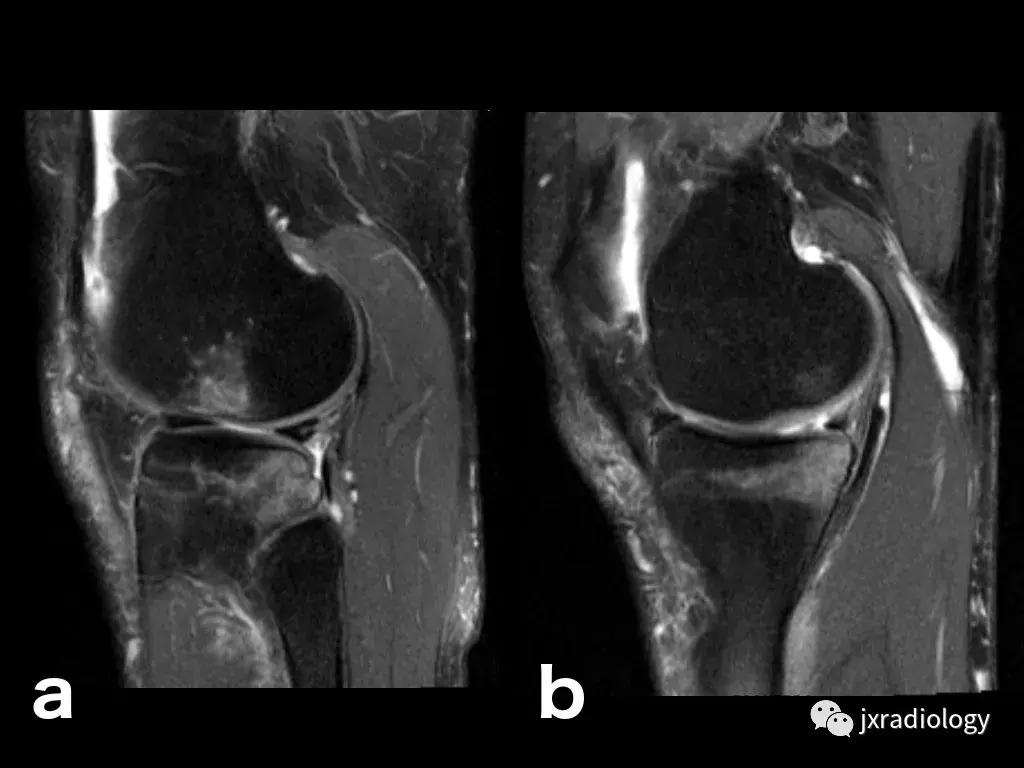

图23:骨巨细胞瘤(PD-FS-WI):也存在肿瘤性骨髓水肿。

图24:骨样骨瘤:在这些良性肿瘤中,水肿可以继发于前列腺素E2引起的炎症反应(a,b:横断位和冠状CT扫描; c,d:横断位T1-WI和冠状位PD-FS-WI)。

图25:短暂性骨髓水肿综合征(短暂性骨质疏松症):30岁女性急性膝部疼痛的矢状位FS-PDWI MR影像显示骨髓水肿,涉及非负重区域股骨外侧髁骨髓水肿在1年内几乎完全自发消退。短暂性骨髓水肿综合征是自限性病变,其表现为与MRI研究中的骨髓水肿证据相关的关节痛。其病因仍不确定。

图26:局限性游走性骨质疏松症(具有位置变化的短暂性骨髓水肿综合征)(连续冠状PD-FS-WI):在一些情况下,在连续MRI上看到骨髓水肿的位置变化,这被称为局限性游走性骨质疏松症(RMO);尽管可以自愈的短暂性骨髓水肿综合征的情况更为常见,但可以在一小部分病例中转移到不同的关节,或者(甚至更罕见)转移到同一关节内的不同部位(关节内转移) ,如关于该患者所见。在这个关节内RMO病例中,没有创伤史,水肿始于股骨内侧髁,3个月后发现转移到外侧髁。